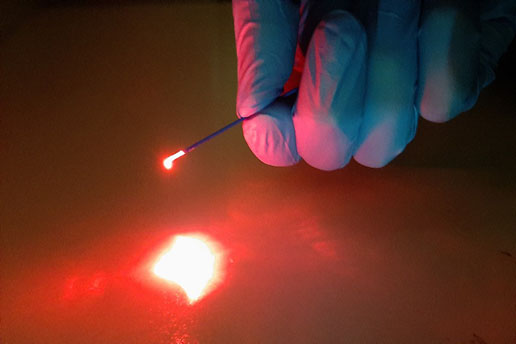

Laser beam quality test, here the uniformity of the fiber probe checked @530nm